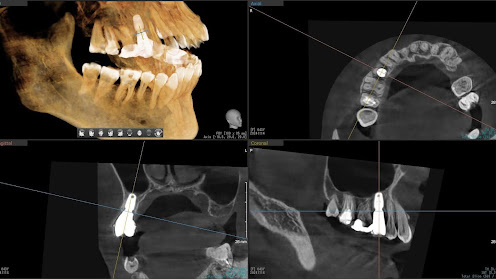

5.左上4番のインプラント抜歯即時埋入、左上6番の上顎既存骨1から2mmのグラフトレスサイナスリフト、左下56の大幅な骨欠損により、下顎神経の損傷を回避するために、ショートインプラントを使用し、左下56にインプラントを埋入し、最終補綴物は、左上456の3ユニットのジルコニアブリッジし、左下56は、ジルコニアの連結冠を装着したケース

Before

枚方市のインプラントの症例

After

M・I 様 女性 70代

症状としては、左下56は、歯周病で欠損したと考えられるが、かなりの骨欠損をともなっていた。左上456に関しては、動揺が大きく、炎症が起き、排膿、および、歯性上顎洞炎を起こしていた。

治療法としては、動揺がひどくなってきて、炎症の症状もあったため、左上56の抜歯を希望。インプラント治療をその後、希望したため、左上4に関しては抜歯即時埋入。左上6に関しては、既存骨1から2mmでインプラント治療が厳しい状態であったが、グラフトレスサイナスリフトを行い、治療期間5か月はかかるということを説明して、インプラント埋入をおこないました。その後、2か月半後、大幅に骨が欠損している下顎56に対して、ショートインプラントを使用して、下顎神経の損傷を避けて、インプラント埋入を終えています。その後2か月後に光学印象で印象を行い、上顎刺億456歯、3ユニットのジルコニアブリッジを装着。下顎左側56に関しては、骨欠損が大きいため、歯冠長がだいぶ長くなるため、ジルコニアの連結冠を装着して治療を終えた。

治療結果は、上顎6に関しては、既存骨が少なく、厳しい治療ではありましたが、5か月で治療を終え、患者様の負担を最小限に抑えるができたと考えます。(従来のサイナスリフトでは、このようなケースでは1年以上、1年程度の治療期間がかかるか、治療が不可能と言われるケースだと考えます。)また、下顎は骨欠損が大きく、下歯槽管のリスクが起きることが考えられますが、ショートインプラントを使用することで安全に治療を行うことができました。

治療の期間・回数:治療期間5か月(上顎456 3ピースブリッジの治療は5か月(上顎既存骨が2mm程度しかなく、骨結合に時間がかかるケースであったために、5か月の治療期間が必要であった。)(左下56に関しては2か月半で治療を終えています。)治療回数は、13回。

治療の価格:1,474,000円(税込)

治療費の内訳:左上46および左下56のインプラント基本料(フィックスチャー及び手術費用、投薬費用、レントゲン費用、インプラント上部費用(アバットメントおよびジルコニアクラウンの費用用)330000円(税込み)×4本分 1320000円(税込)。左上5ジルコニアポンテック費用88000円(税込)。オプション費用、左上4抜歯即時埋入加算(人工骨費用を含む)+グラフトレスサイナスリフト費用 33000円(税込)、左上6グラフトレスサイナスリフト費用 33000円(税込)

治療のリスクや副作用:手術後に、痛みや腫れ、出血、合併症などを引き起こす可能性があります。噛む感覚がご自身の歯と異なる場合があります。見た目がご自身の歯と異なる場合があります。手術後にメインテナンスを継続しないと、インプラントが抜け落ちる可能性があります。